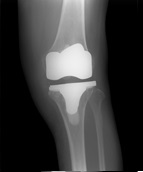

3.画像診断

- X-P所見(別紙参照):FTA左167°

- 骨折の特徴や手術法の特徴などを理解した上で、治療手技を考えていく必要がある。主なリスクは担当医に確認する

| 術前 | 術後 | 経過 |

![]() |

| FTA | 大腿骨と脛骨の長軸のなす大腿脛骨角。正常は約176度 |

| Mikulicz線 | 大腿骨頭中心から足関節中心を結ぶ下肢機能軸は立位での下肢荷重線を表し、正常では膝関節のほぼ中央を通過する |